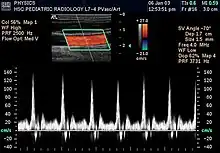

- Modo Doppler: Este modo hace uso del efecto Doppler, para visualizar el flujo sanguíneo.

- Doppler color: La información sobre la velocidad y dirección del flujo en tiempo real se representa con unidades de color.[23]

- Doppler espectral: En vez de utilizar colores, muestra la circulación de la sangre en un gráfico. Se puede utilizar para mostrar el nivel de bloqueo de un vaso sanguíneo.[23]

- Doppler dúplex: Utiliza ecografía convencional para formar imágenes de los vasos sanguíneos y los órganos, las cuales serán convertidas posteriormente en un gráfico similar al Doppler espectral.[23]

- Doppler de onda continua: En esta prueba, las ondas sonoras se envían y reciben de forma continua. Permite medir de manera más precisa la sangre que fluye con mayor rapidez.[23]

Ecografía Doppler

La ecografía doppler o simplemente eco-Doppler es una variedad de la ecografía tradicional, basada por tanto en el empleo de ultrasonidos, en la que aprovechando el efecto Doppler, es posible visualizar las ondas de velocidad del flujo que atraviesa ciertas estructuras del cuerpo, por lo general vasos sanguíneos, y que son inaccesibles a la visión directa.[24] La técnica permite determinar si el flujo se dirige hacia la sonda o si se aleja de ella, así como la velocidad de dicho flujo. Mediante el cálculo de la variación en la frecuencia del volumen de una muestra en particular, por ejemplo, el de un flujo de sangre en una válvula del corazón, se puede determinar y visualizar su velocidad y dirección. La impresión de una ecografía tradicional combinada con una ecografía Doppler se conoce como ecografía dúplex.[1]

La información Doppler se representa gráficamente con un Doppler espectral, o bien como una imagen usando Doppler direccional o un power Doppler (Doppler no-direccional). La frecuencia Doppler cae en el rango audible y puede escucharse utilizando altavoces estéreo, produciendo un sonido pulsátil distintivo.